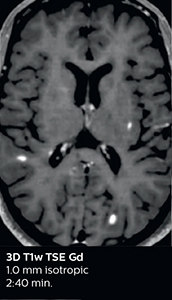

The abbreviated MS protocol for brain is only around 9 minutes, so in case of suspected multiple sclerosis, one or two more advanced sequences may be added, such as PSIR (phase sensitive inversion recovery) or susceptibility-weighted sequences to help us make more confident diagnoses in these inflammatory cases.

In this example, the optional 3D multishot susceptibility weighted sequence with 0.6 mm isotropic voxels is 2 lesions with a central vein sign (arrows) and one lesion with a phase-rim sign (arrowhead). The total scan time, including SmartBrain and axial PD/T2 3mm, is 11:10 min. and is 18:30 min. with the optional 3D PSIR and 3D SWI multishot included.